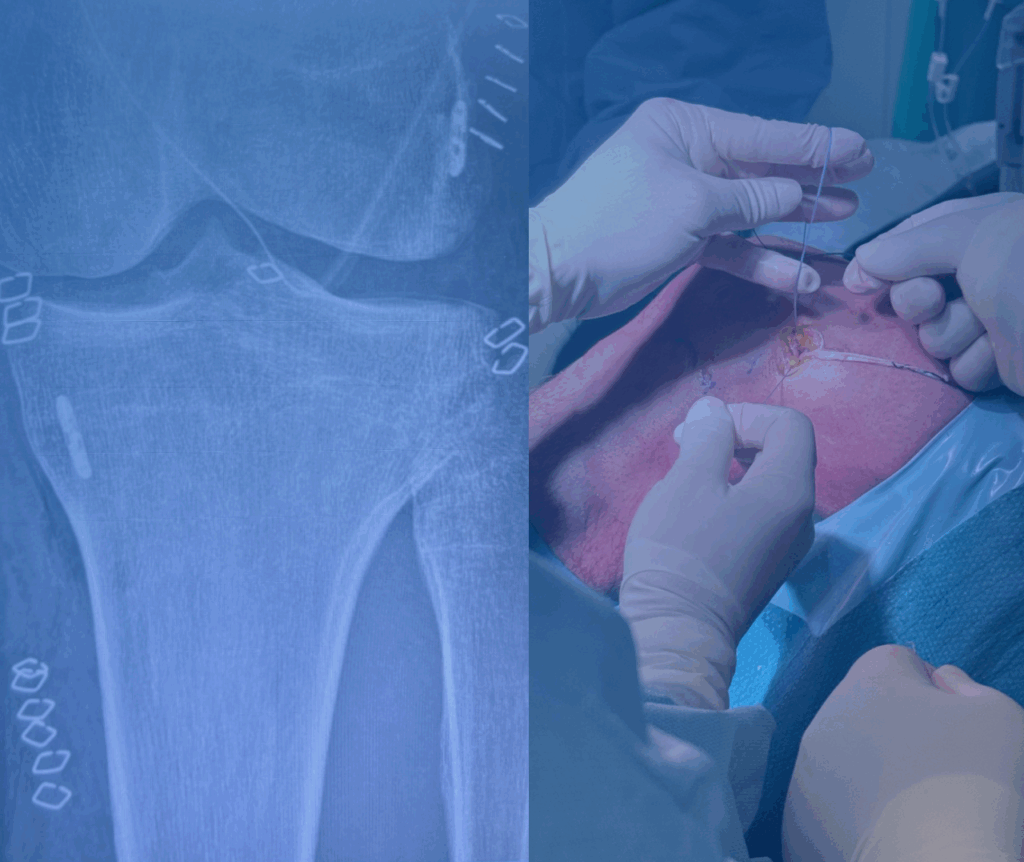

Si svolge nella ricerca scientifica e nella pratica chirurgica in linea con l’evoluzione di tecniche sempre meno invasive, per la cura delle patologie della spalla, del ginocchio e della Traumatologia dello Sport.

Mettersi in discussione costantemente attraverso lo studio, la ricerca e il confronto con professionisti nazionali e internazionali permette di esercitare una chirurgia sempre più moderna e personalizzata con risultati sempre più sicuri.